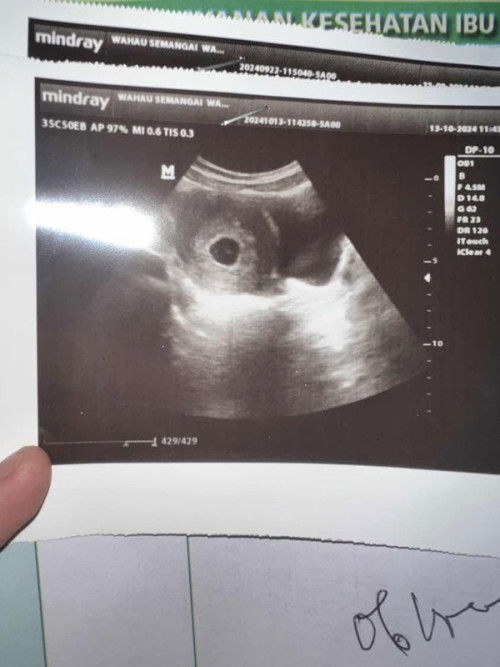

#SeriusTanya #ingintahu #firstmom mohon doanya bunda” semua🙏🏻 sebelumnya memang sering flek yg pudar tdk terlalu kelihatan nah baru aja tdi fleknya lumayan bnyakk warna coklat kemerahan. minggu lalu sdh usg kantung dan janin alhamdulillah sdh ada untuk djj blm disuruh balik bulan depan. hasil usg dokter bilang usianya beda 3 mingguan lebih dari hpht dan terancam keguguran. karna flek yg lumayan bnyk ini saya konsultasi lgi ke dokter lewat chat dan disarankan usg 2 minggu kemuadian. saya cuma diresepin asam folat sm anti pendarahn dari dokter tdk ada penguat. smoga di usg selanjutnya janin saya baik” sj sdh ada djj dan berkembang dgn sehat Aamiin ya Allah semuanya sy pasrahkan kpdMu🤲🏻

#SeriusTanya #ingintahu #mohonpencerahan disini ada yg sama? saya sering nge flek mulai uk 6week sekarang 10week baru aja tadi keluar lendir warna kuning kecoklatan dikit, sering keputihan kuning juga.. kmrin usg dokter bilang usianya baru 6w padahal dri hpht sdh 9w, janin sdh ada tp blm ada djj nya disuruh balik lgi bulan dpn. mohon doanya ya semua